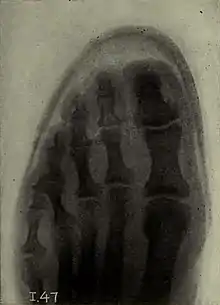

El Dedo del Pie de Morton (también conocido simplemente como Dedo de Morton o Pie de Morton) es una condición congénita en la cual el metatarsiano del dedo gordo es corto comparado con el metatarsiano del segundo dedo del pie. Esta condición es un tipo de braquimetatarsia.

La señal principal es tener un segundo dedo del pie más "largo" que el dedo gordo, en realidad, no se padece un segundo dedo más largo, más bien se trata de un primer dedo más corto de lo normal.

Este rasgo consiste en la presencia de un segundo dedo del pie el cual es más largo que el dedo gordo del pie.[1]